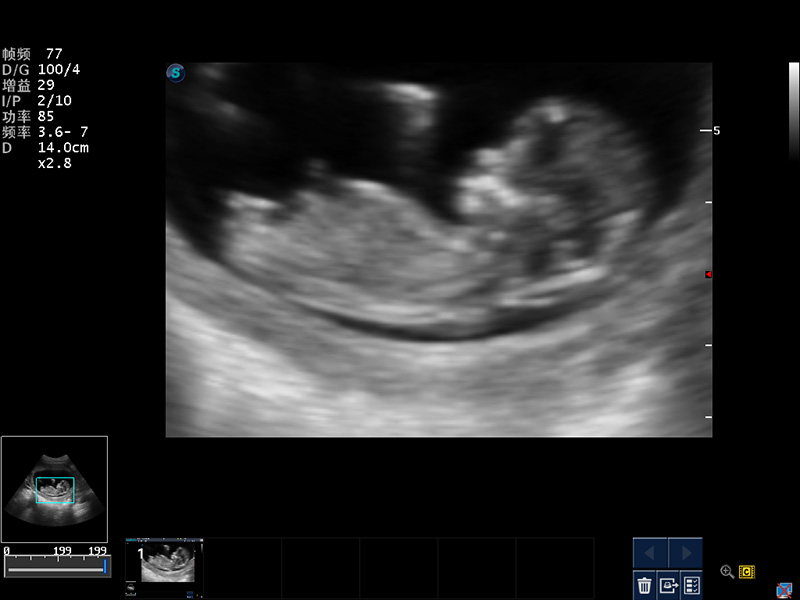

随着开立医疗超声设备核心技术的提升及临床应用领域的拓展,公司2014年全新推出全数字S12系列超声彩色多普勒诊断仪,真正意义上实现了“小身材、大智慧”的设计理念,外观小巧灵活,内在性能强大。即兼顾了全身临床应用,又拓展了多种高级成像功能,轻松满足临床应用日趋多元化的需求。

4D成像